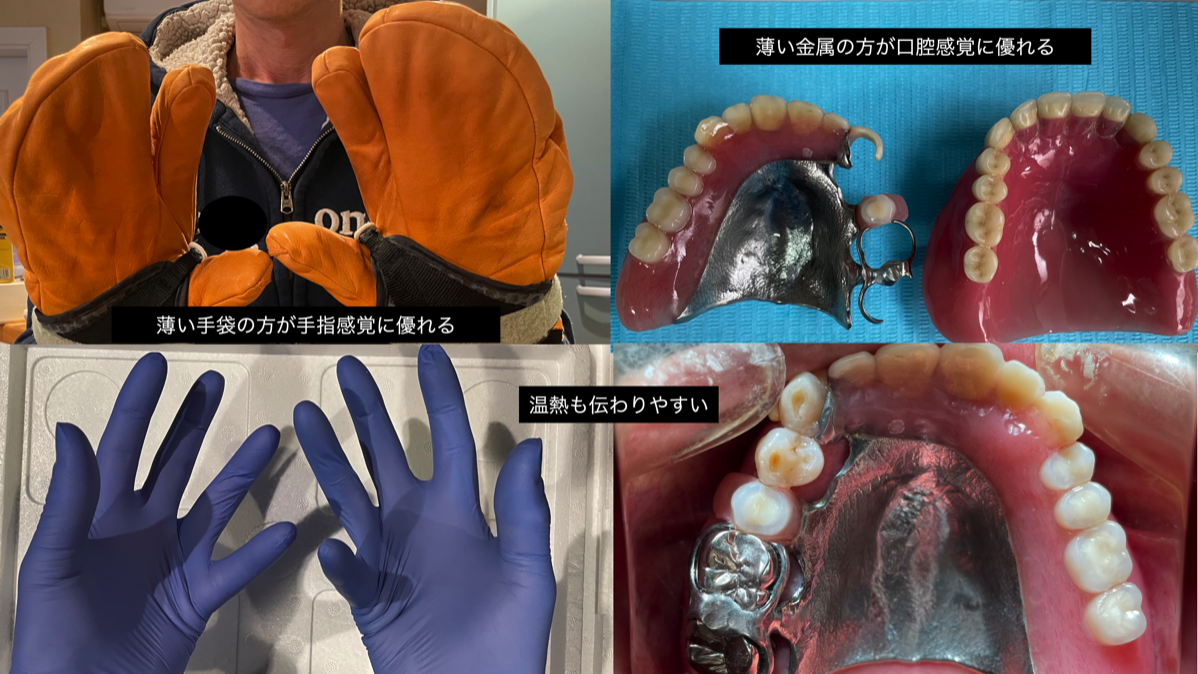

もし歯を失って義歯での治療を選択した場合には、感覚に優れる義歯が良いと考えられます。

認知症の予防で指遊びや手指を使うことは広く知られています。

同様に口腔の感覚を維持することも極めて大切です。

表情筋をしっかりと動かして顔の表情を作り楽しくおしゃべりをする。おいしい食事をしっかり咬んで飲み込む。毎日実践してこそ認知症予防です。

もし歯を失って義歯での治療を選択した場合には、感覚に優れる義歯が良いと考えられます。